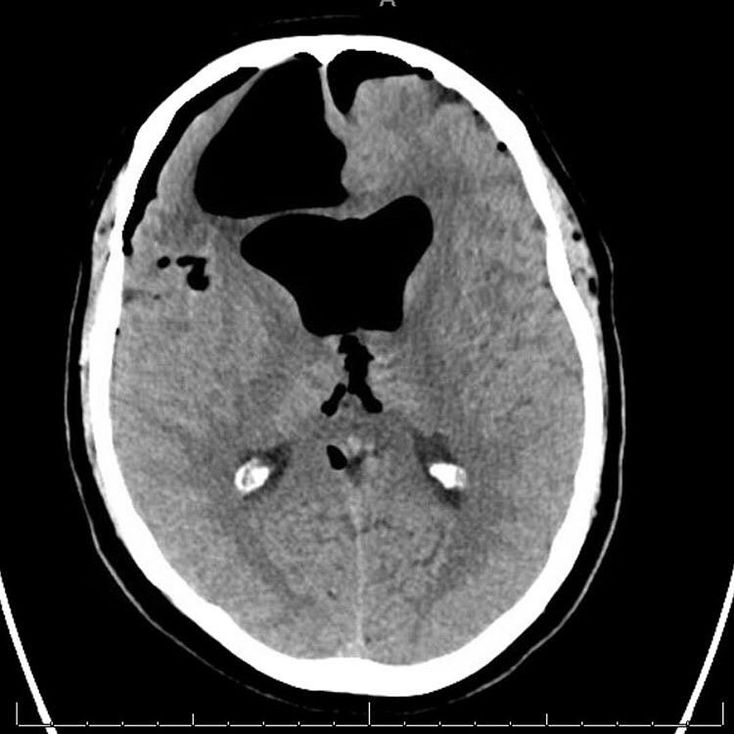

This set of photos was discovered in a patient with altered mental status and a recent sinus infection. CT scan of the brain demonstrated a tension pneumocephalus, which is air trapped in the subdural space of the brain, causing mass effect over the underlying brain parenchyma. This is not a common complication with a sinus infection, and is usually associated with disruption of the skull: after head and facial trauma, tumors of the skull base, after neurosurgery or otorhinolaryngology, and rarely, spontaneously. This patient did improve with just antibiotics and supportive care although in many situations this is a neurosurgical emergency requiring surgical decompression.